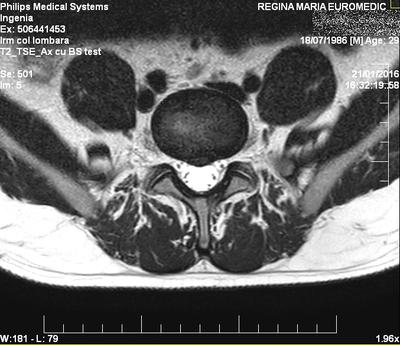

My name is Daniel, i am 30 years old, and i recently (about a month ago) had a lumbago episode due to my recurring lumbar disc hernia at L5-S1.

Third occurence:

- Until january 2016 (this year), i was feeling good. After the winter, i started feeling pain in my lower back. I started taking painkillers (almost regularly). One morning when i was in the bathroom, i sneezed and "heard" something popping in my back. I knew it was going to some harm. In 15-20 minute i started having pain in my back, and progressively i felt like i have not strength in my lower back. I had the "luck" to sneeze again, and that was the final take for my L5-S1 disk. The pain resulted forced me to rest in bed, and take more pain killers. I went to a clinic and did a session of streching on a horizontal table. Also i visited a chiropractor and did a session. When i did the chiropactic i didn't had any sciatica pain (only back pain) and the chiropractition practically streched everything with ease i must say. After a few days, my

back suddenly stopped hurting, i was feeling like a new born.

I went to work for two weeks (standing in a chair at the desk). In the last week i started having pain in my right leg and buttock when i tried to move around. After the final week at work (and with driving and all) i was feelind very bad (intense pain in leg and bottock on the right side right above the knee), probably my disk had migrated into the spinal canal, iritating the S1 right nerve root.

Good luck, Daniel. I hope this contributes. It's not a large herniation.